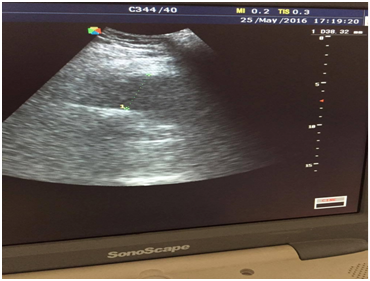

There were no significant blood test abnormalities, except elevated C-reactive protein. Electrolytes and renal function tests were normal. Performed color Doppler ultrasound of the lower leg vessels revealed an image with a greatest diameter of 38.32mm within the topography of the SFA, poorly-defined limits and mural thrombus. These characteristics suggested a ruptured aneurysm of the SFA (Figure 3). Computed tomography angiography (CTA) revealed ruptured aneurysm of right SFA with a diameter of 34mm (Figure 4 and 5).

Figure 3 Ruptured aneurysm of the SFA.